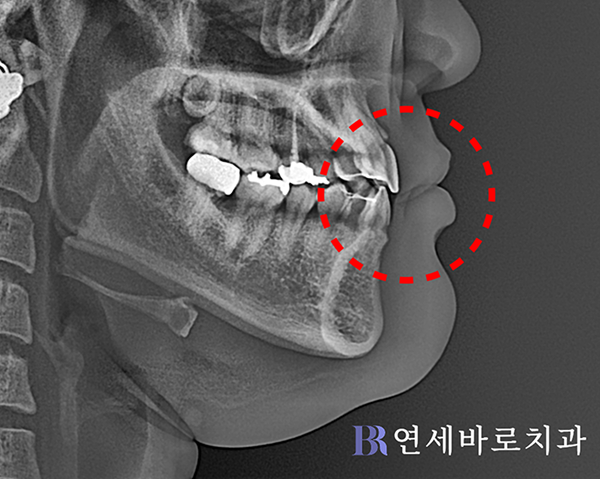

아랫니가 윗니보다 더 후방에

위치할 수 있게 만들었고,

그만큼 살짝 나온 아랫입술도

뒤로 들어가게 되었습니다.

본원에서는 외모개선에 관하여

사전에 충분히 상담해보고

교정의 방향을 설정하였습니다.

그렇기 때문에 지나칠 정도의

안모 변화를 방지하면서

좋은 결과를 이끌어냈습니다.